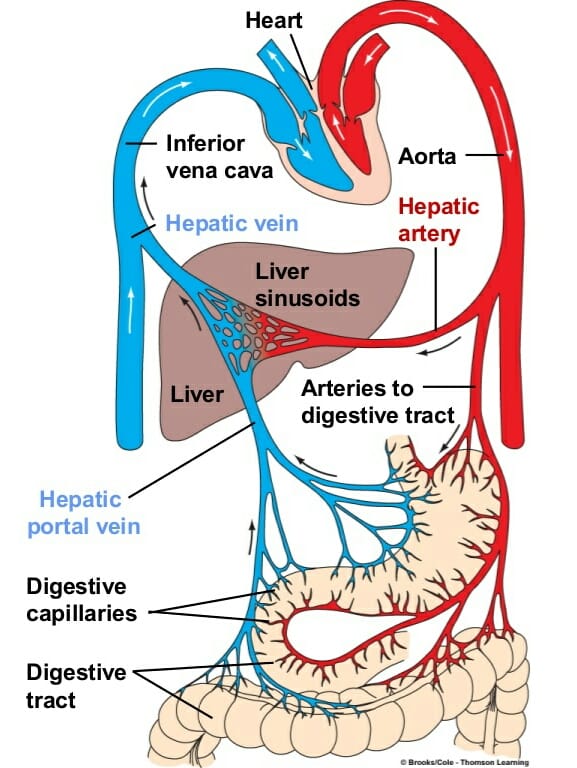

Hepatic Portal Circulation Physiology Explained YouTube

A P Hepatic Portal Circulation Diagram Quizlet